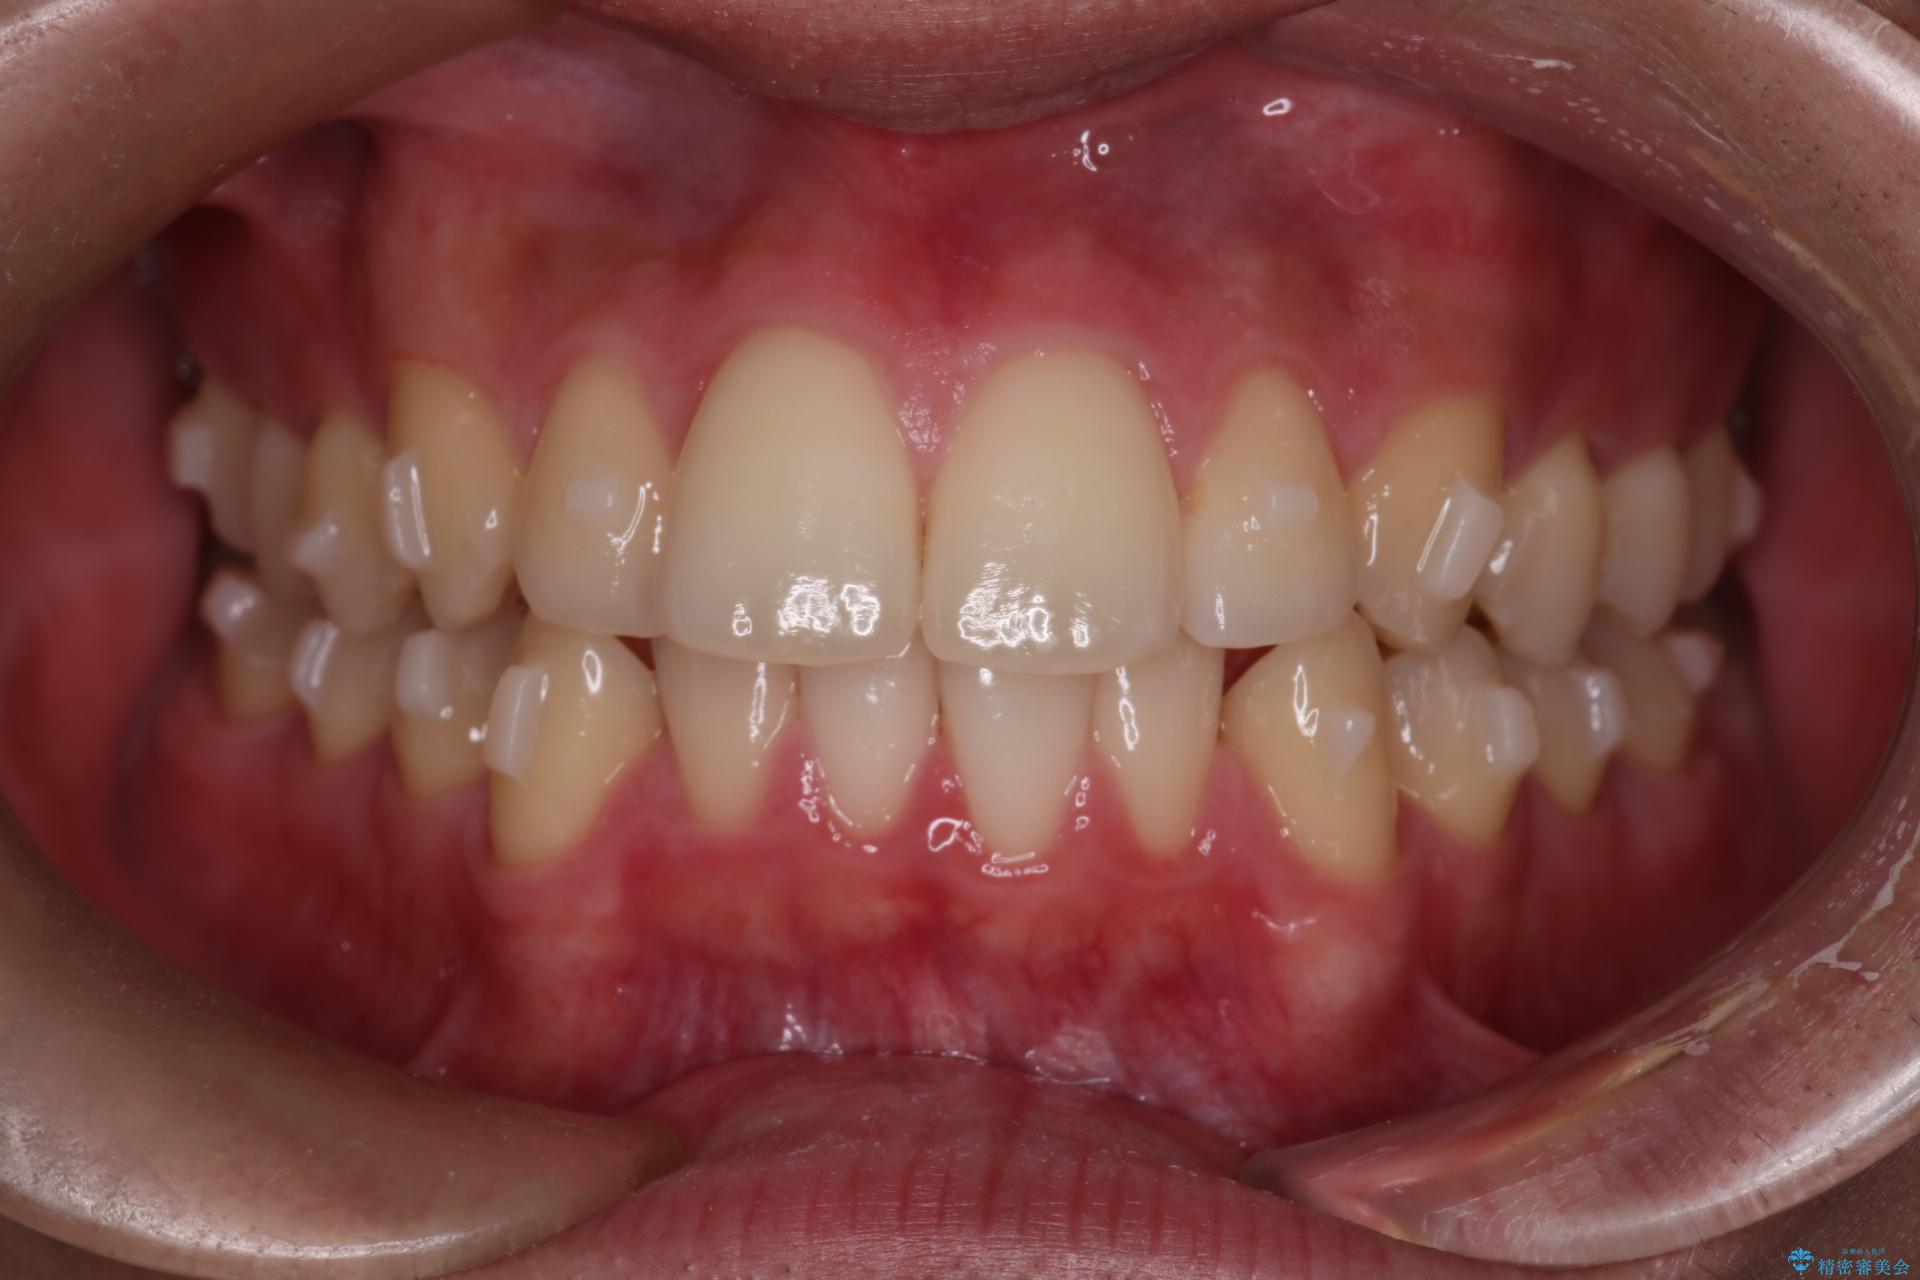

患者様はシミュレーション通りに歯が動くのかと心配されていました。

可能な限り計画通りに歯を動かすために、マウスピース1枚あたりの使用時間を長めに使っていただきました。

そのため、多少治療期間が延びましたが、リファイメント(マウスピースの再発注)なしで終了することができました。